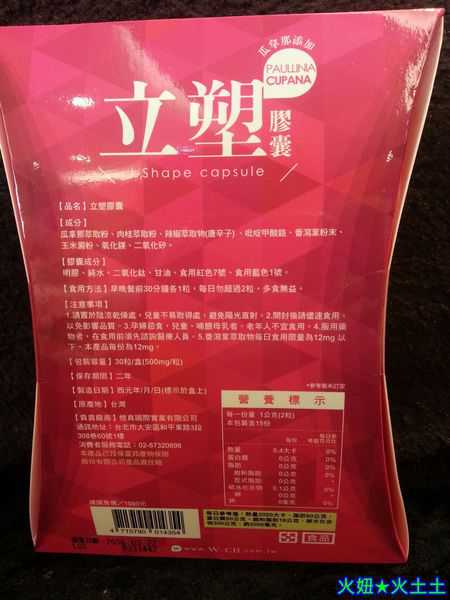

Supercut塑魔纖立塑膠囊的成分有:瓜拿那萃取粉、肉桂萃取粉、辣椒萃取物(唐辛子)、吡啶甲酸鉻、番瀉葉粉末、玉米澱粉、氧化鎂、二氧化矽。

之前上過相關課程,成分表是依照每項成分的多寡來排列順序,排在最前面的就是產品的主要成分!

食用方式:早晚餐前30分鐘各1粒,每日不超過2粒。(多食無益)

番瀉葉萃取物每日食用限量為12mg以下,